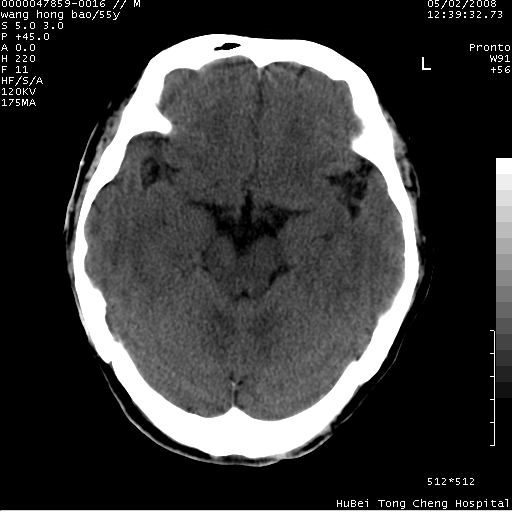

以下是引用dyqct在2008-5-3 23:36:00的发言:[br]桥前池区可疑蛛网膜囊肿。其它未见明显异常。建议做mri。

以下是引用qiushi在2008-5-4 10:10:00的发言:[br]鞍上池前缘突出影为双侧额叶直回;箭头所指为双侧正常之人字缝.[br]桥前池区可疑表皮样囊肿或蛛网膜囊肿,必要时mri

以下是引用zjzjr在2008-5-4 14:50:00的发言:[br]桥前池区可疑蛛网膜囊肿。其它未见明显异常。建议做mri。